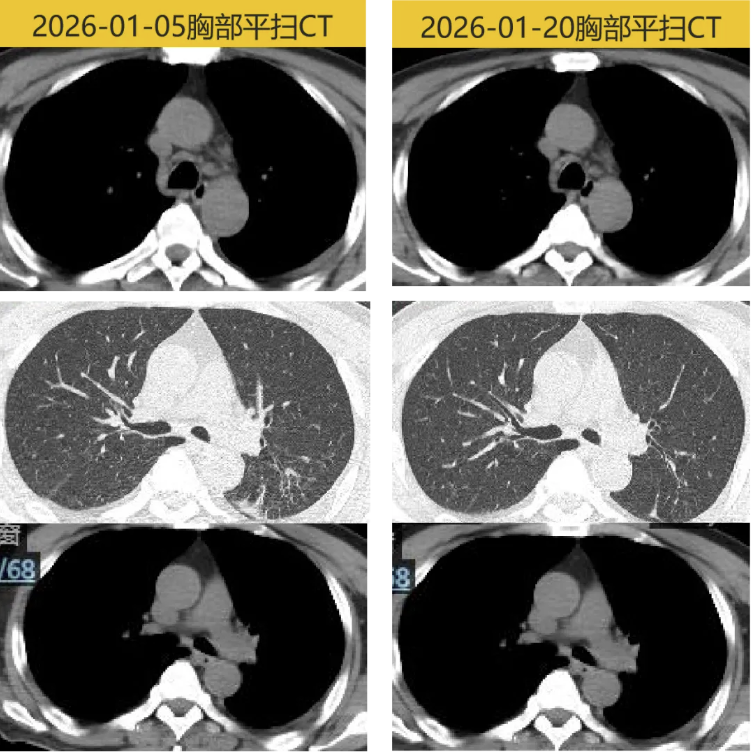

2026-01-05 随访WBC 4.72×10^9/L,N 66.4%;hsCRP 5.8mg/L,ESR 66mm/h,PCT 0.38ng/mL;ALT/AST 91/69U/L,D二聚体 1.01mg/L;炎症降至正常。胸部平扫CT:左侧胸腔积液较前25-12-24减少;两肺上叶新增炎症,治疗后随访;左下肺渗出、部分不张,较前稍好转,纵隔小/稍大淋巴结(较前变小)。

2026-01-20 出院后体温平,无咳嗽咳痰,胸腔引流管无引流液;WBC 7.13×10^9/L,N 63.0%;hsCRP 0.6mg/L,ESR 13mm/h,PCT 0.08ng/mL;ALT/AST 28/33U/L,D二聚体 1.09mg/L;炎症标志物均降至正常,胸部平扫CT:左侧胸腔积液较前26-01-05减少;两肺上叶炎症,较前好转;左下肺渗出、部分不张,较前好转,纵隔小/稍大淋巴结(较前相仿)。予拔出胸腔引流管。嘱继续阿莫西林克拉维酸0.457g bid+甲硝唑0.4g tid口服,2周后感染病科门诊随访。